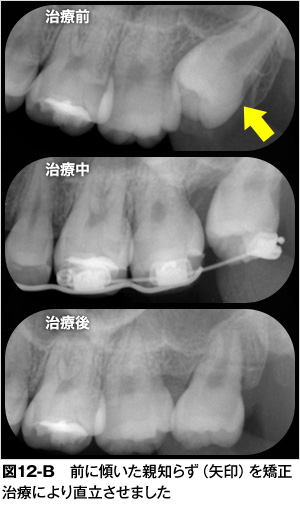

| 5. | 矯正治療で親知らずを正しい位置に動かすことができる:親知らずの生える方向が悪くても矯正治療によりきちんとかめるように治すことができます。写真は上顎の親知らずの生える方向が通常よりも前方に向いてしまったために手前の第二大臼歯に接触し、親知らずがこれ以上生えられない状態です。(図12-A)親知らずの生える場所が十分にあり、下顎にかみ合うべき親知らずも正常に生えているので、上顎の親知らずを矯正治療で移動させました。(図12-B)矯正治療後は上下の親知らずがかみ合って良好に経過しています。(図12-C)矯正治療は歯を動かす治療ですがどのような状況でも可能とは限りません。矯正治療で治せるかどうかは歯科医師に相談することをお勧めします。 |

矯正治療で親知らずを正しい位置に動かすことができる:親知らずの生える方向が悪くても矯正治療によりきちんとかめるように治すことができます。写真は上顎の親知らずの生える方向が通常よりも前方に向いてしまったために手前の第二大臼歯に接触し、親知らずがこれ以上生えられない状態です。